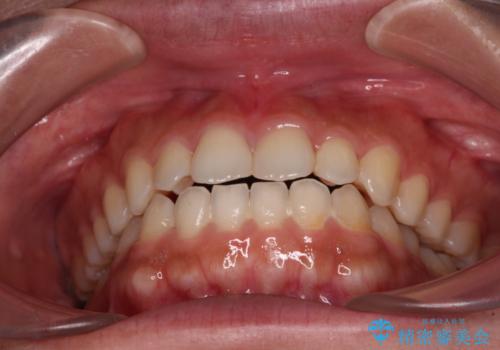

インビザラインを用いた上顎の部分矯正

- 上顎前歯の叢生を気にして来院された患者様です。

下顎前歯や上下奥歯の咬み合わせには殆ど問題がないため、上顎前歯のみを矯正する治療を提案しました。

ワイヤー装置でもインビザラインでも可能でしたが、前歯のみをきれいに排列するのであればインビザラインの方が仕上がりが良いので、インビザライン・ライトにて治療を行うこととしました。